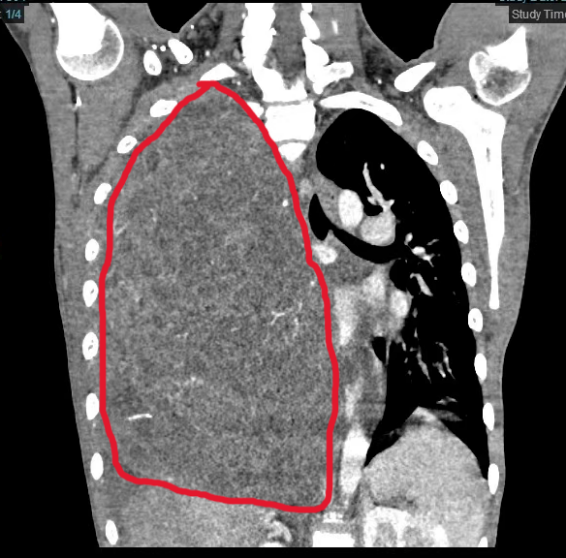

小宇体内的纵膈肿瘤尺寸达29×27×15厘米,长满右侧胸腔并延伸到左侧,将心脏从正常位置挤压到左侧胸壁边缘,并严重压迫周边脏器、影响心肺功能。更棘手的是,肿瘤血供丰富,与周围组织粘在一起,手术切除风险极高,极易引发致命性大出血。

由于肿瘤占据双侧胸腔大部、心脏严重受压移位,常规切口视野不足。而且儿童胸腔容积更小,器官发育不成熟,手术难度与风险显著增高。经过多次术前讨论,手术团队决定采用Clam-shell(蛤壳式)双侧前胸横切口,能更好的暴露肿瘤,为切除提供最佳条件,该手术方法通常用于肺移植手术。

3月13日,麻醉科副主任医师郭东东及团队全程严密护航,丁建勇和儿科医院心胸外科副主任医师张文波密切配合,精细操作,逐层剥离,最终成功将肿瘤完整切除,术中出血不到100ml。切下的肿瘤重达7斤3两,超过了成年人头颅大小。术后小宇心肺压迫即刻解除,顺利转入康复治疗,本周即可出院。